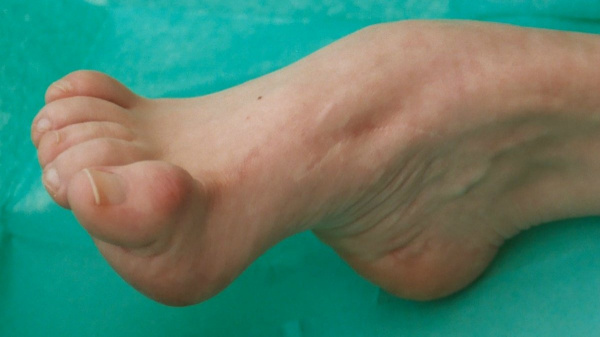

(Справа) Клиническая фотография того же пациента вскоре после УЗИ. Расщепление позвоночника и косолапость повторяют находки при УЗИ в 20 нед. (Слева) УЗИ плода с дистальным артро-грипозом. Запястья в стойком согнутом положении, пястно-фаланговые суставы и кисти рук разогнуты. Кроме того, определяются двусторонняя косолапость и выраженная атрофия мышц нижних конечностей (по сравнению с подкожной жировой клетчаткой).

(Справа) Тот же случай. Клиническая фотография новорожденного. Ультразвуковые находки подтверждены. При выявлении двусторонней косолапости необходимо внимательно исследовать верхние конечности. (Слева) УЗИ плода во II триместре. Синдром множественных птеригиумов и водянка плода (не показана). Фиксированные контрактуры кистей, кожная складка в области локтевого сустава и выраженная косолапость.

(Справа) Клиническая фотография. Тот же случай. К характерным признакам синдрома множественных птеригиумов относят кожные складки в области локтевых и коленных суставов.